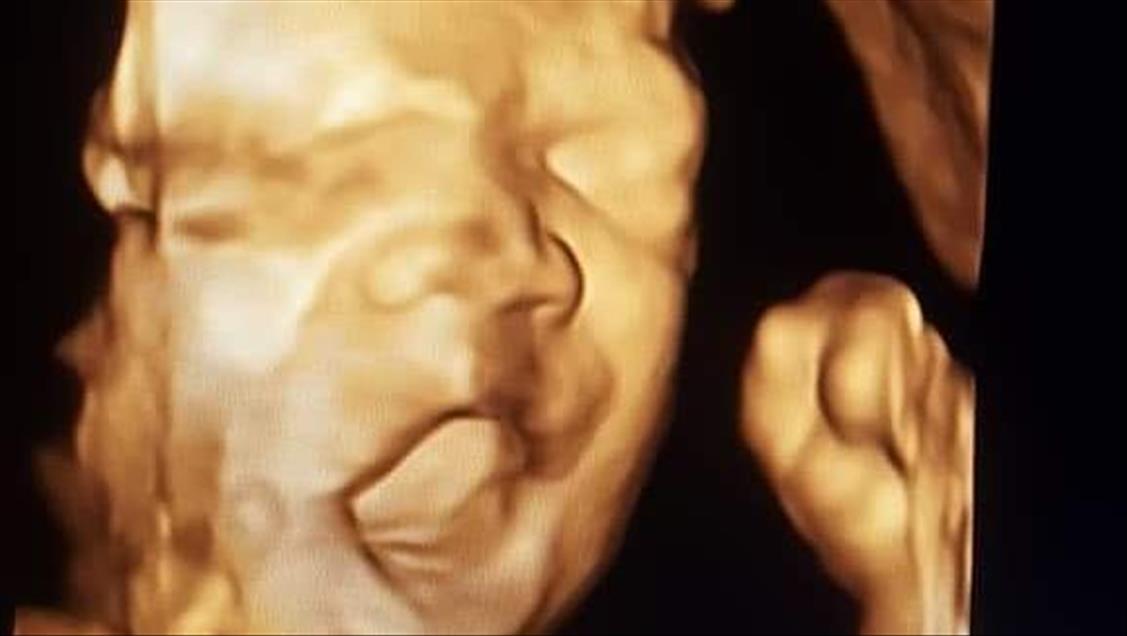

Anne karnındaki bebeklerin ilginç ultrason görüntülerini yakalayan ve bu görüntülerden özel bir köşe oluşturan kadın hastalıkları ve doğum uzmanı Doç. Dr. Gökalp Öner'in, yaklaşık 4 bin fotoğraflık koleksiyonu bulunuyor. Doç. Dr. Öner, AA muhabirine yaptığı açıklamada, sadece bir koleksiyon sahibi olmanın değil, anne ve babalara güzel bir hatıra oluşturmanın mutluluğunu da yaşadığını belirterek, "Doğumdan sonra aileler bizi ziyarete geldiği zaman kendi köşeleri olsun ve orada fotoğraf çektirelim istedik. Böylece, yaklaşık 4 bin ultrason fotoğrafına ulaştık." dedi. ( Müzahim Zahid Tüzün - Anadolu Ajansı )